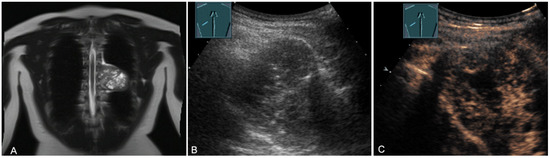

Figure 17.

A young patient with tumor formation in the paravertebral mediastinum on CT (provided by Prof. Dr. Andreas H. Mahnken, Marburg, Germany) (A), B-mode US (B), and CEUS (C), surgically confirmed as schwannoma.

Figure 18.

A young patient with tumor formation in the paravertebral mediastinum on magnetic resonance imaging (provided by Prof. Dr. Andreas H. Mahnken, Marburg, Germany) (A), B-mode US (B), and CEUS (C), surgically confirmed as a benign giant cell tumor.